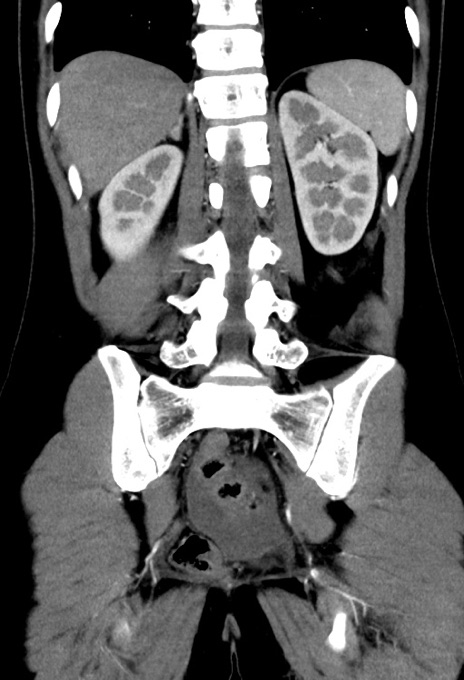

症例17(冠状断像)

【症例】20歳代女性

【主訴】嘔吐、下腹部痛

【現病歴】昨日夕食後に嘔吐し下腹部痛が出現。本日になっても嘔吐持続し改善しないため来院。

【身体所見】意識清明、BT 37.2℃、BP 108/67mmHg、腹部:平坦、やや硬、下腹部正中から右にかけて圧痛あり、反跳痛軽度あり、tapping pain(+)。

【データ】WBC 13600、CRP 14.94